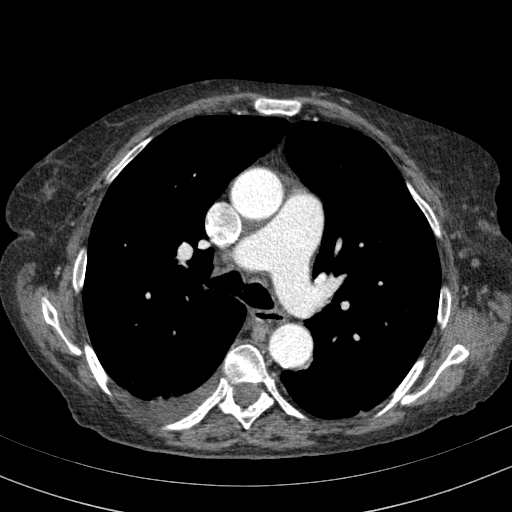

Generated VENOUS CT scan (A→B translation)

Full window (WL 1023.5, WW 4095 β†’ Low βˆ’1024, High +3071)

Actual HU range: [-1024.0, 1137.2]